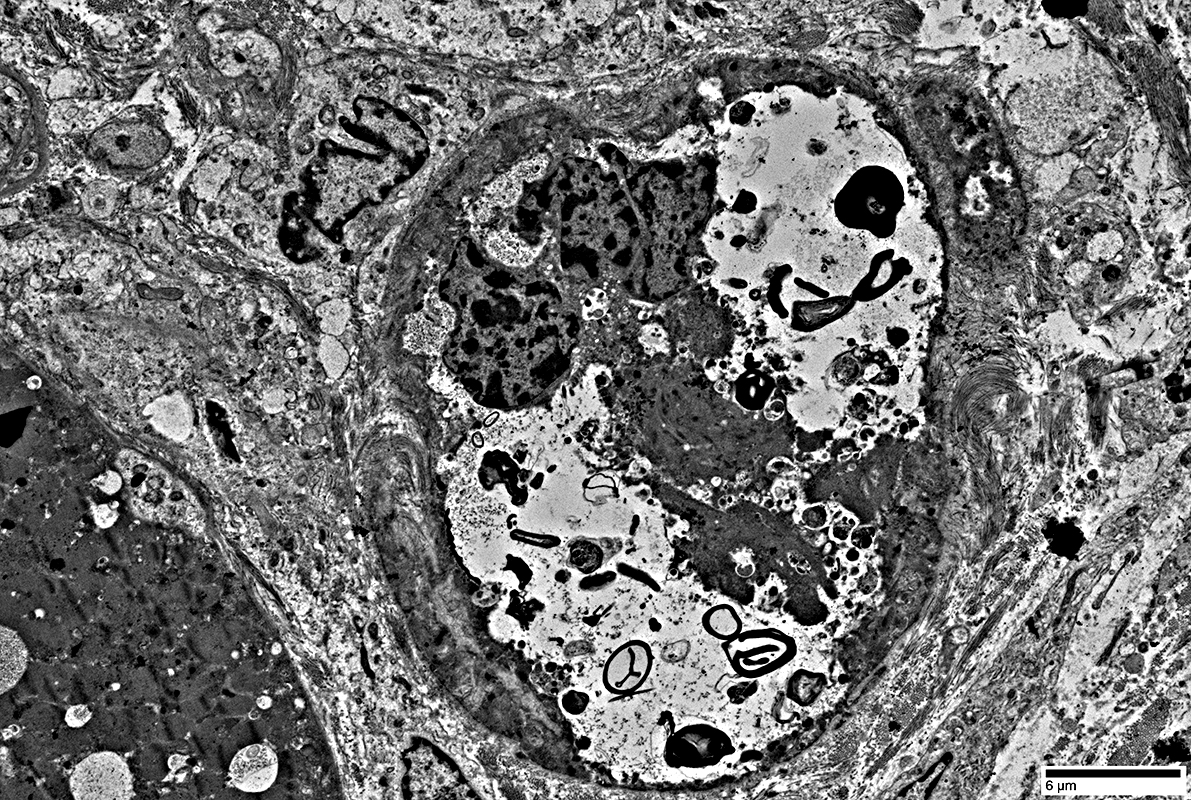

Autophagic Vacuoles

Multiple small vacuoles in small muscle fiber (Yellow arrow)

Large autophagic vacuole: Budding from the surface of a large muscle fiber (White arrow)

Multiple small vacuoles in small muscle fiber

Lymphocytes

Location: Endomysium; Surround muscle fiber

Large vacuole replacing most cytoplasm in small muscle fiber (Above)

Contents of vacuole (Below)

Autophagic Vacuoles: Different contents

Filaments: Varied densities

Myeloid figures

Aggregates

From: R Schmidt